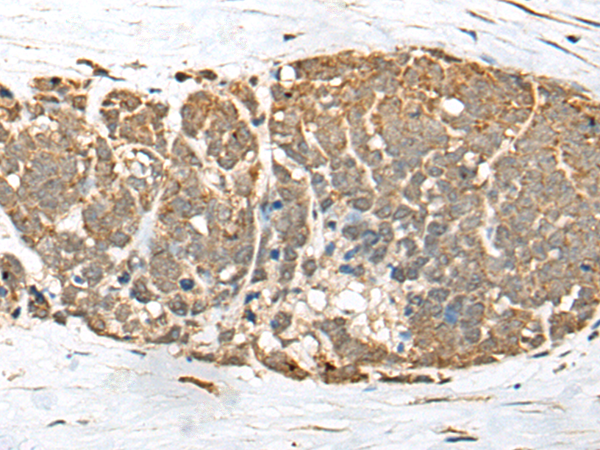

IHC positive control:

Human thyroid cancer